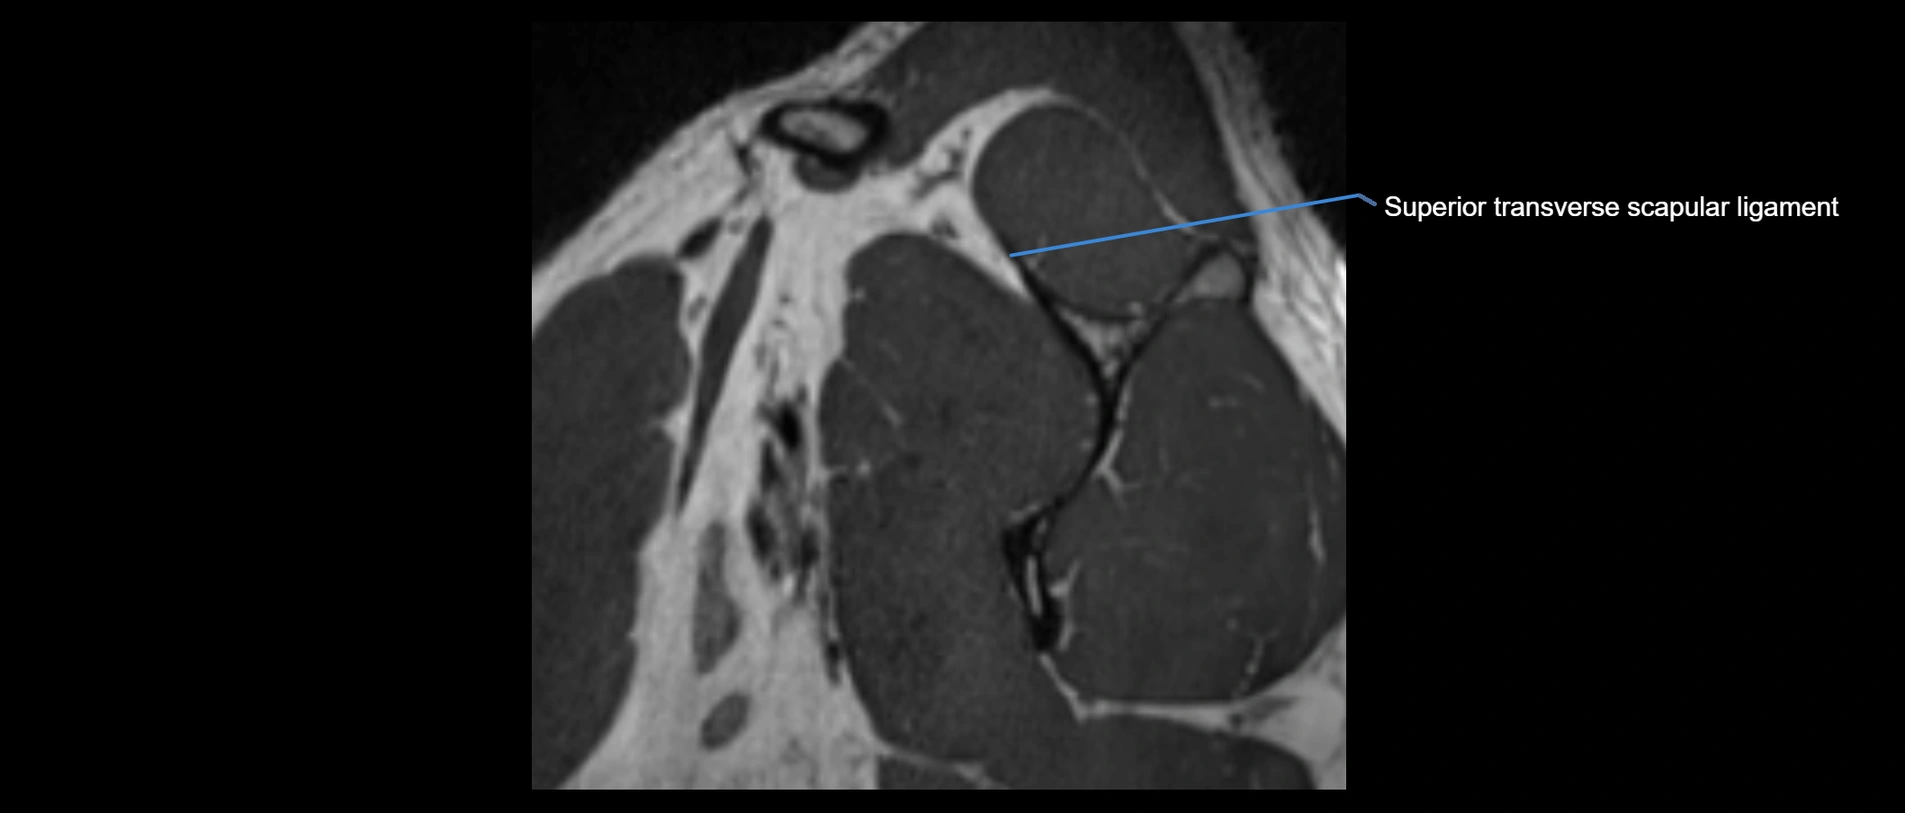

CT image

image

CT Appearance

Non-Contrast CT:

• Ligament: Not directly visualized due to small size and low density.

• Bony landmarks: Lateral clavicle and acromion clearly seen; cortical margins well defined.

• Pathology: Detects fractures, joint subluxation, osteophytes, and degenerative changes.

• Alignment assessment: Evaluates AC joint spacing and clavicular displacement.